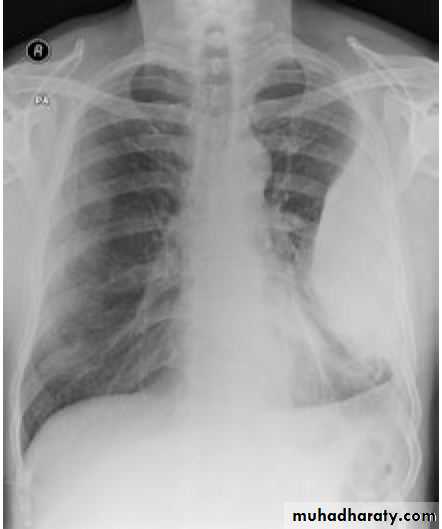

This frontal CXR reveals complete collapse ofthe right lung due to a massive right pneumothorax, which is also shiftingthe heart and other mediastinal structures to the left, (a tension pneumothorax).

In tension PNX, the findings are progressive breathlessness associated with a marked tachycardia, hypotension, cyanosis and tracheal displacement away from the side of the silent hemithorax.

Tension PNX rapidly causes mediastinal shift and, if untreated, will lead to impaired venous return and cardiovascular collapse.

Death from respiratory or cardiovascular collapse may occur.